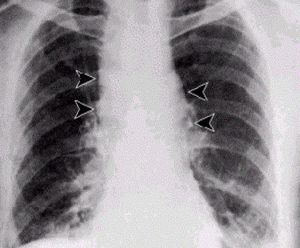

إنَّ الأعراض الأولية للجمرة الخبيثة الاستنشاقية inhalation anthrax تكون خفيفة ولا نوعية وقد تشمل حمى ووعكة وسعال خفيف أو ألم بالصدر؛ وبعد 3-5 أيام تحدث أعراض حادة للضائقة التنفسية وظهور اتساع الـمَنْصِف في الصورة الشعاعية، ما في ذلك الاختناق ، ضيق التنفس الحاد ، hypoxemia ، diaphoresis وزرقة وصدمة ثم الوفاة بعد فترة قصيرة. والارتشاح البلورى شائع ، ويمكن أن ترى تسربات أحيانا على الصدر بالأشعة السينية. ويقدر الحد الأقصى لمعدل إماتة الحالات إلى اكثر من 85 ٪ ، والعلاج في وقت مبكر بمضادات الميكروبات العدوانية إلى جانب الرعاية الداعمة قد يقلل من نسبة الوفيات الكبيرة. الجمرة الخبيثة يمكن علاجها في المرحلة المبكرة ، ولكن الوفيات لا تزال مرتفعة على الرغم من المعالجة المضادة للجراثيم إذا كان بدأ العلاج بعد بداية الأعراض التنفسية. في البلدان التي تتوطن فيها الفقيرة ، وحيث قيمة اللحوم من الحيوانات التي قد ماتت بشكل غير متوقع تفوق المخاطر المتصورة من المرض التي قد تنجم عن تناوله . الجمرة الخبيثة الابتلاع ليست من غير المألوف ، ويمكن أن تتخذ شكل الجمرة الخبيثة في البلعوم الفمى، ولكنهاأكثر شيوعا كجمرة خبيثة في الجهاز الهضمي. في الاولى الآفة في تجويف الفم ، على مخاطية الشدق واللسان واللوزتين ، أو جدار البلعوم الخلفي.التهاب الحلق واعتلال العقد اللمفية الإقليمية في الرقبة ، مع وذمة واسعة النطاق قد تؤدي الى انسداد القصبة الهوائية ، هي السمات الغالبة في وقت مبكر. في حالة الجمرة الخبيثة في الجهاز الهضمي ، الآفة قد تكمن في أي نقطة على طول الأمعاء ميببة تقرح وذمي على نطاق واسع ، مما يؤدى إلى نزيف ، و ثقب ، واستسقاء واسع النطاق. ابتلاع الجمرة الخبيثة ليست مميتة دائما ، ولكن ، حتى مع العلاج الوفيات يمكن أن تكون عالية ، مع تطور تسمم الدم والصدمة والغيبوبة والموت. فترة الحضانة بشكل عام 3 -- 7 أيام.